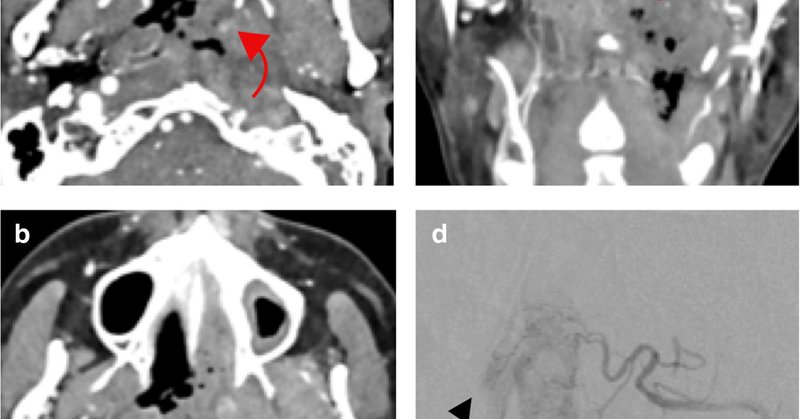

👏Superstar #radres alums @traviscaton @NandMiskinMD @gunetty collaborated on this great article published by @ASER_ERad 👏#soproud #congrats🥂 https://t.co/cqMMvVjY5k

link.springer.com

Emergency Radiology - Acute hemorrhage in the head and neck (AHNH) is life-threatening due to asphyxiation and hemorrhagic shock. When conservative measures fail, some patients benefit from...